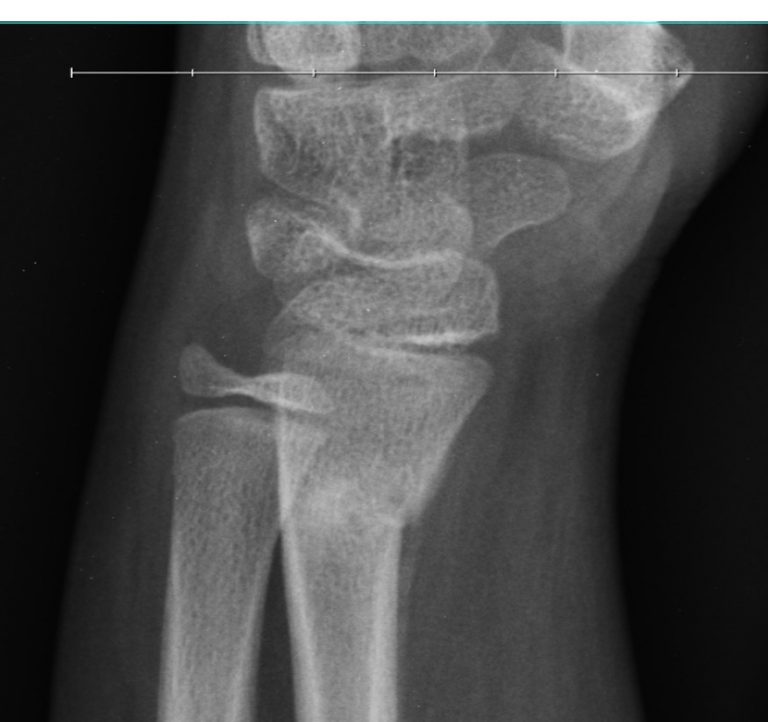

Torus Fracture Of The Radius | Radiology Case | Radiopaedia.org

Torus fracture of the radius | Radiology Case | Radiopaedia.org radiopaedia.org